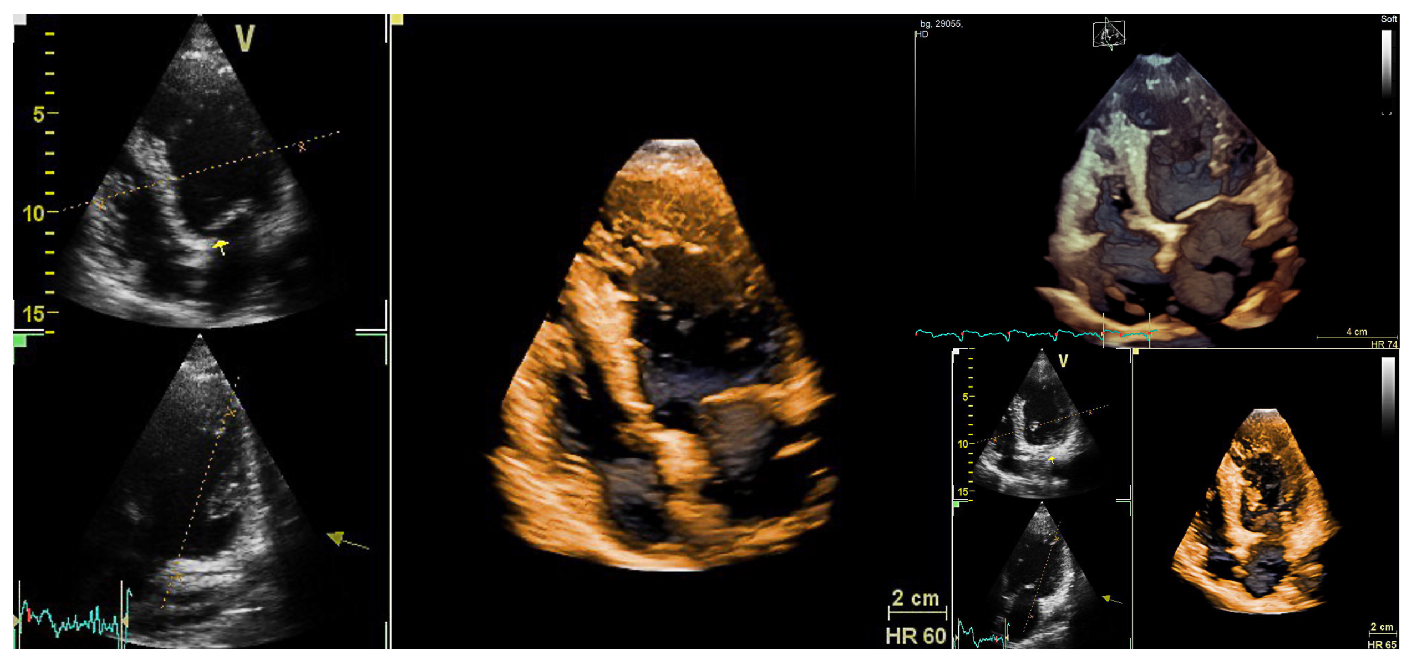

Case Report Patient A

Figure 1. Noncompacted myocardium in Lamin mutation. Echocardiographic examination of patient A at the age of 37 showing highly trabeculated and mildly dilated left ventricle. In short axis, in end-systole a noncompacted/compacted ratio of 2.4 was calculated; this in addition to a borderline ejection fraction of 52% suggested a diagnosis of left ventricular noncompaction. The left ventricular diastolic function was normal. The right ventricle was not dilated and showed normal function. No valvular abnormalities were detected.